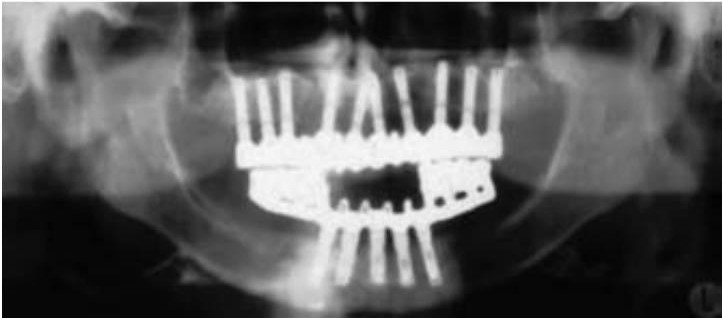

El apretamiento aumenta el riesgo de fallo mecánico, como fractura de la porcelana, descementación de restauraciones, fractura del tornillo del pilar, fractura del cuerpo del implante y pérdida de hueso crestal (fig. 6-18).